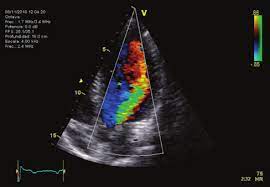

La ecocardiografía se destaca como una herramienta diagnóstica clave, ya que permite evaluar las características principales de la enfermedad. Este método puede determinar si la lesión afecta la raíz aórtica proximal y qué patología valvular está presente. Dado que la severidad de la regurgitación aórtica puede progresar con el tiempo, es crucial realizar evaluaciones anuales del tamaño y la función del ventrículo izquierdo para definir el momento adecuado para la sustitución valvular en casos de regurgitación severa. La guía de valvulopatías de la ACC/AHA de 2020 establece criterios específicos para evaluar la severidad de la regurgitación aórtica.

El pre-cierre de la válvula mitral, observable en la ecocardiografía, se considera una indicación para una intervención quirúrgica urgente. La imagen ecocardiográfica puede mostrar el cierre anormal de la válvula mitral y la alta presión diastólica del ventrículo izquierdo, confirmando la necesidad de una corrección quirúrgica inmediata para abordar la regurgitación aórtica aguda y aliviar el estrés hemodinámico severo sobre el corazón.